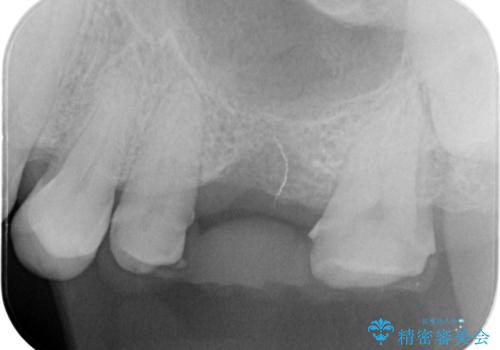

- 左上の奥歯を何とか保存していた患者様です。

今回、残していた歯根から歯茎が大きく腫れ、長期的な予後を期待できないことを考慮し、抜歯してブリッジでの治療を行いました。